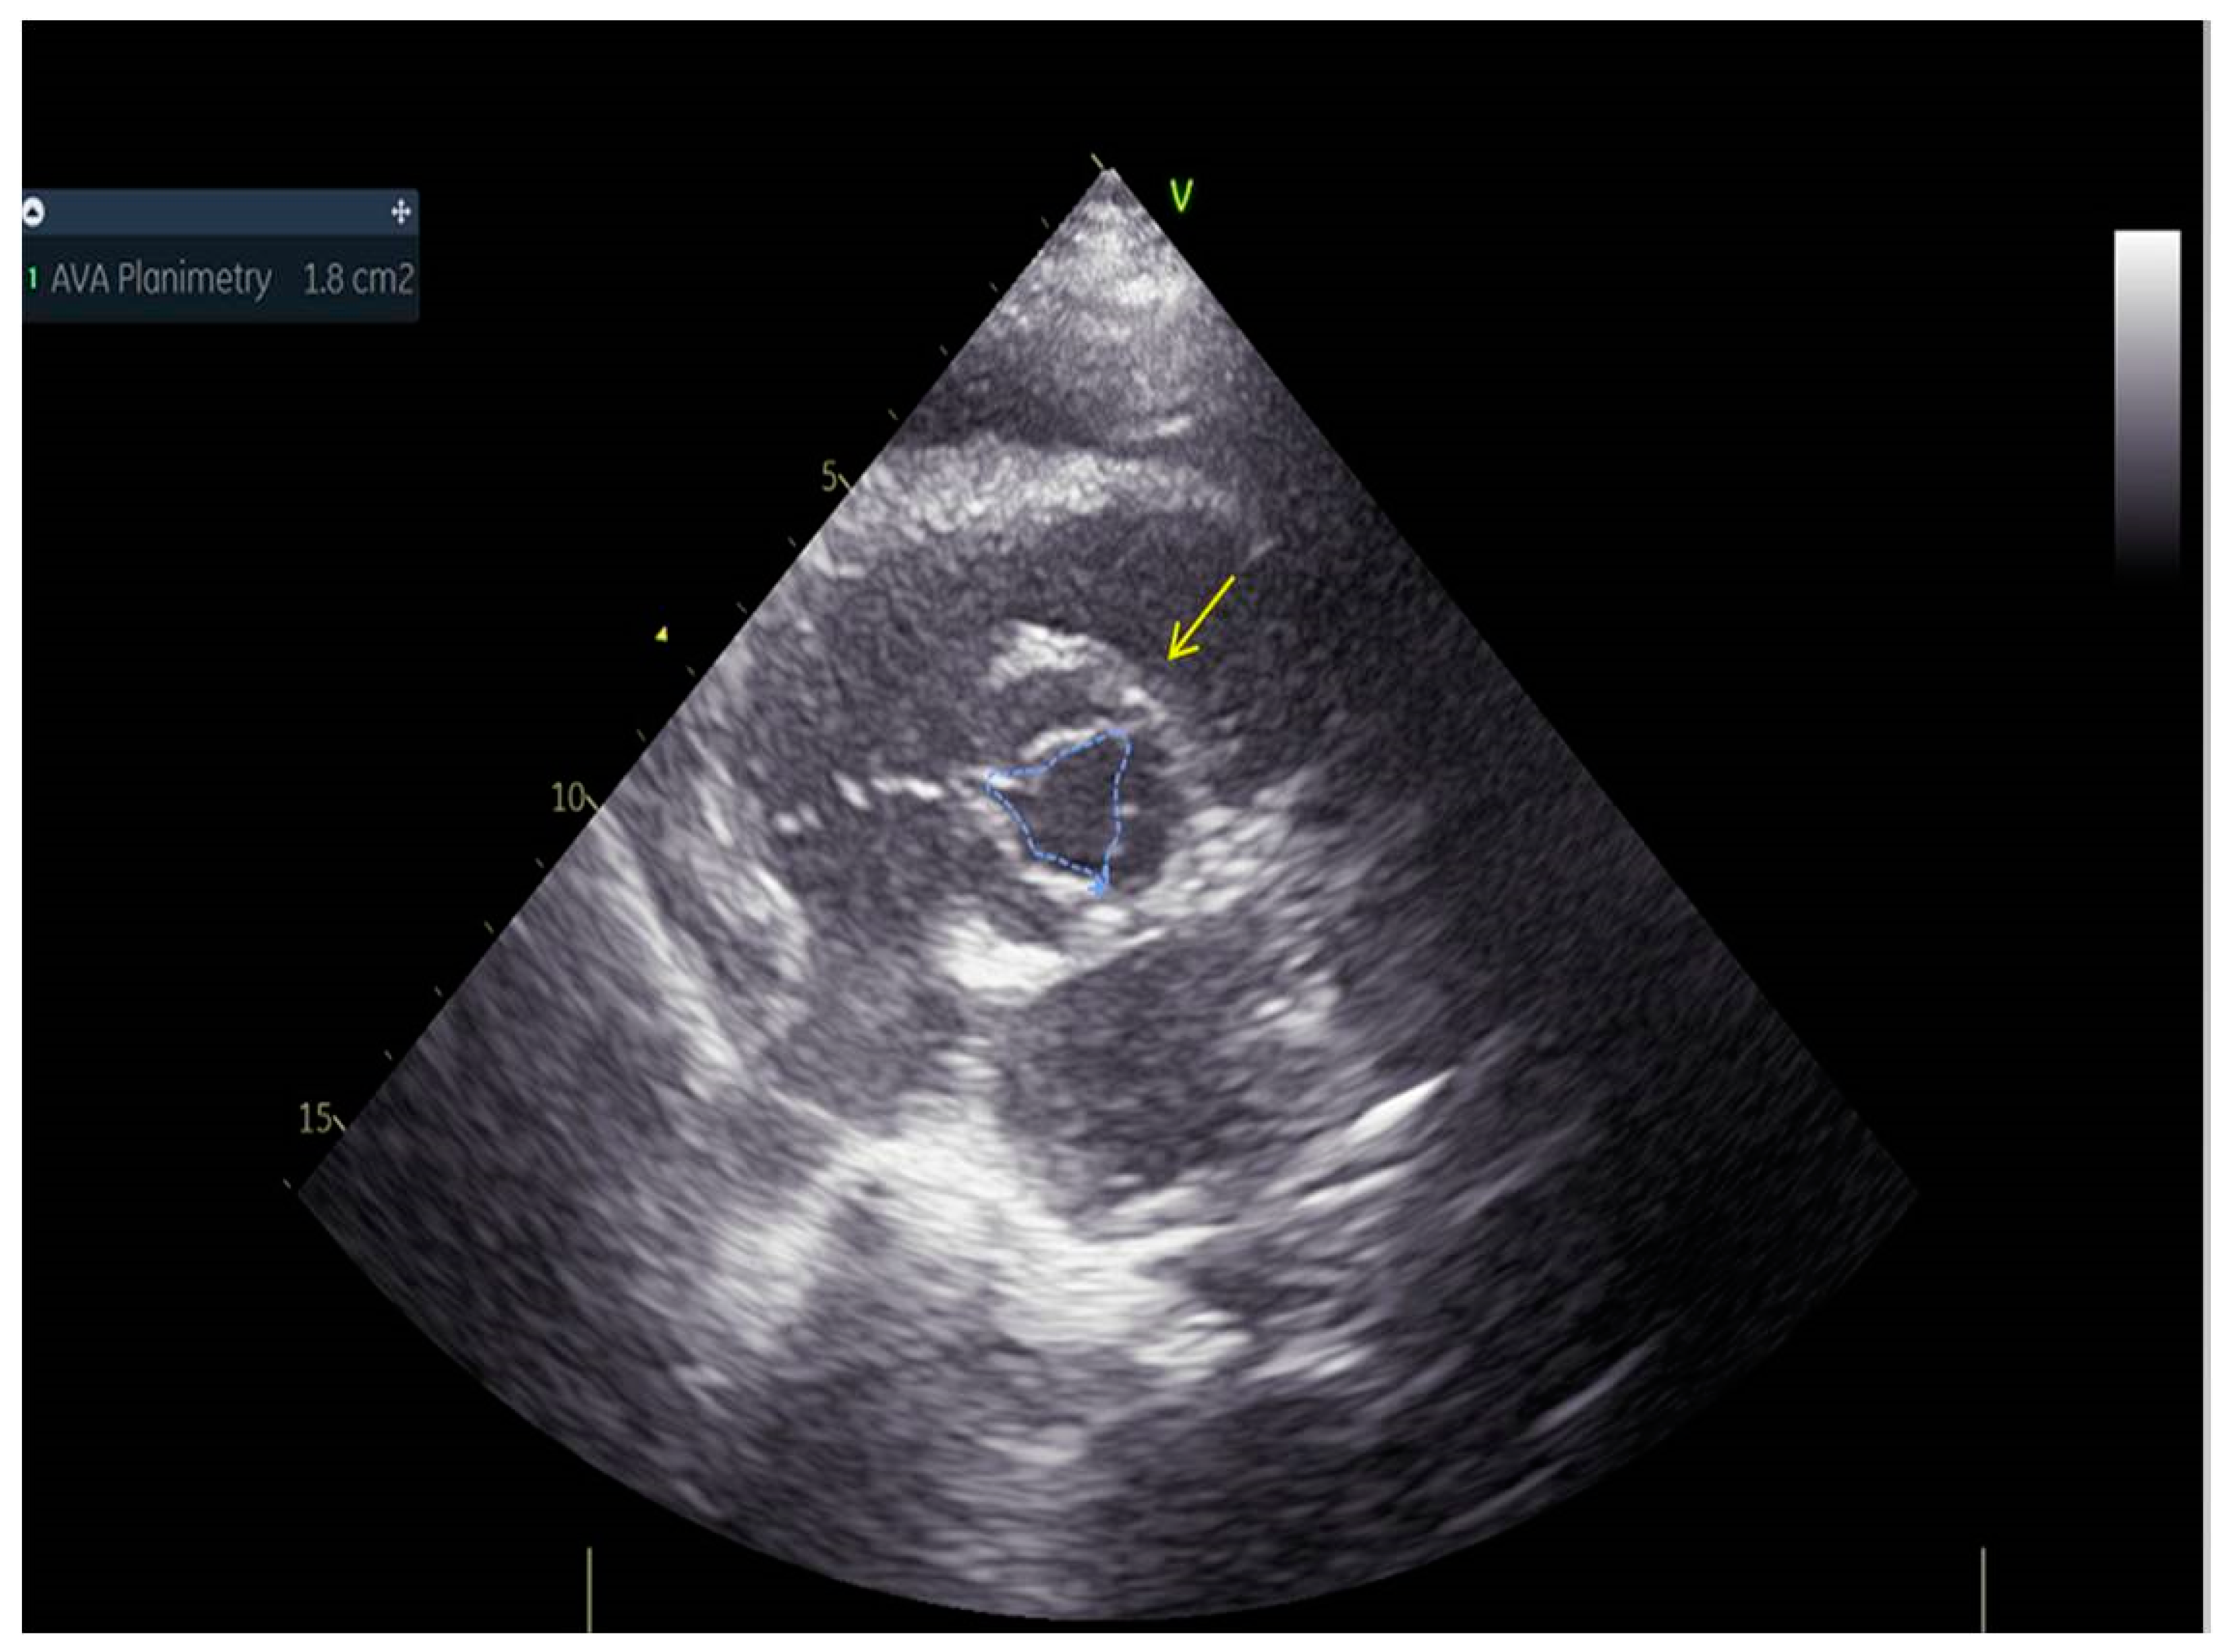

As a result, the patient was referred to a specialized medical institution. Upon admission, the patient was conscious, confused, hypotensive (TA 80/50 mmHg), with a heart rate of about 110/min, and showing clinical signs of hypoperfusion and cardiogenic shock, Killip IV. The medical staff administered sedation, inserted an endotracheal tube, and placed her on invasive mechanical ventilation. The patient was given crystalline solutions, inotrope, and vasopressor medication. An urgent echocardiographic examination was performed due to a rough systolic murmur over the precordium. It revealed akinesia of all medioapical segments of the left ventricle and akinesia basally inferior, where the myocardium was fibrously altered. Other hyperkinetic basal segments formed a dynamic obstruction of the left ventricular outflow tract (LVOTO) with turbulent flow and moderate mitral regurgitation (Figure 2 and Figure 3). The maximum gradient above the LVOT was 160 mmHg (Figure 4). The aortic valve area was 1.8 cm2 (Figure 5). The ejection fraction of the left ventricle (LVEF) was estimated to be 25%. The examination also revealed pericardial effusion with separation between pericardial layers along the right ventricle and atrium of up to 1.2 cm, but without any signs of tamponade.

Figure 5.

Aortic valve area was 1.8 cm2.